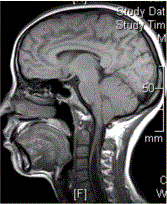

问题 患者女,40岁,手部麻木数年。MR显示如下图。 可能的诊断为

选项 A.Chiari畸形Ⅰ型 B.Chiari畸形Ⅱ型 C.脊髓空洞症 D.Dandy-walker畸形 E.VHL

答案 A